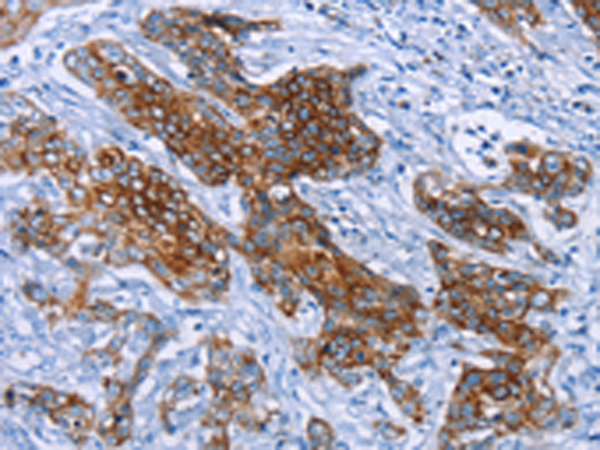

分类: 科研抗体货号: P01606别名: NS; E2IG3; NNP47; C77032应用: WB,IHC反应种属: Human